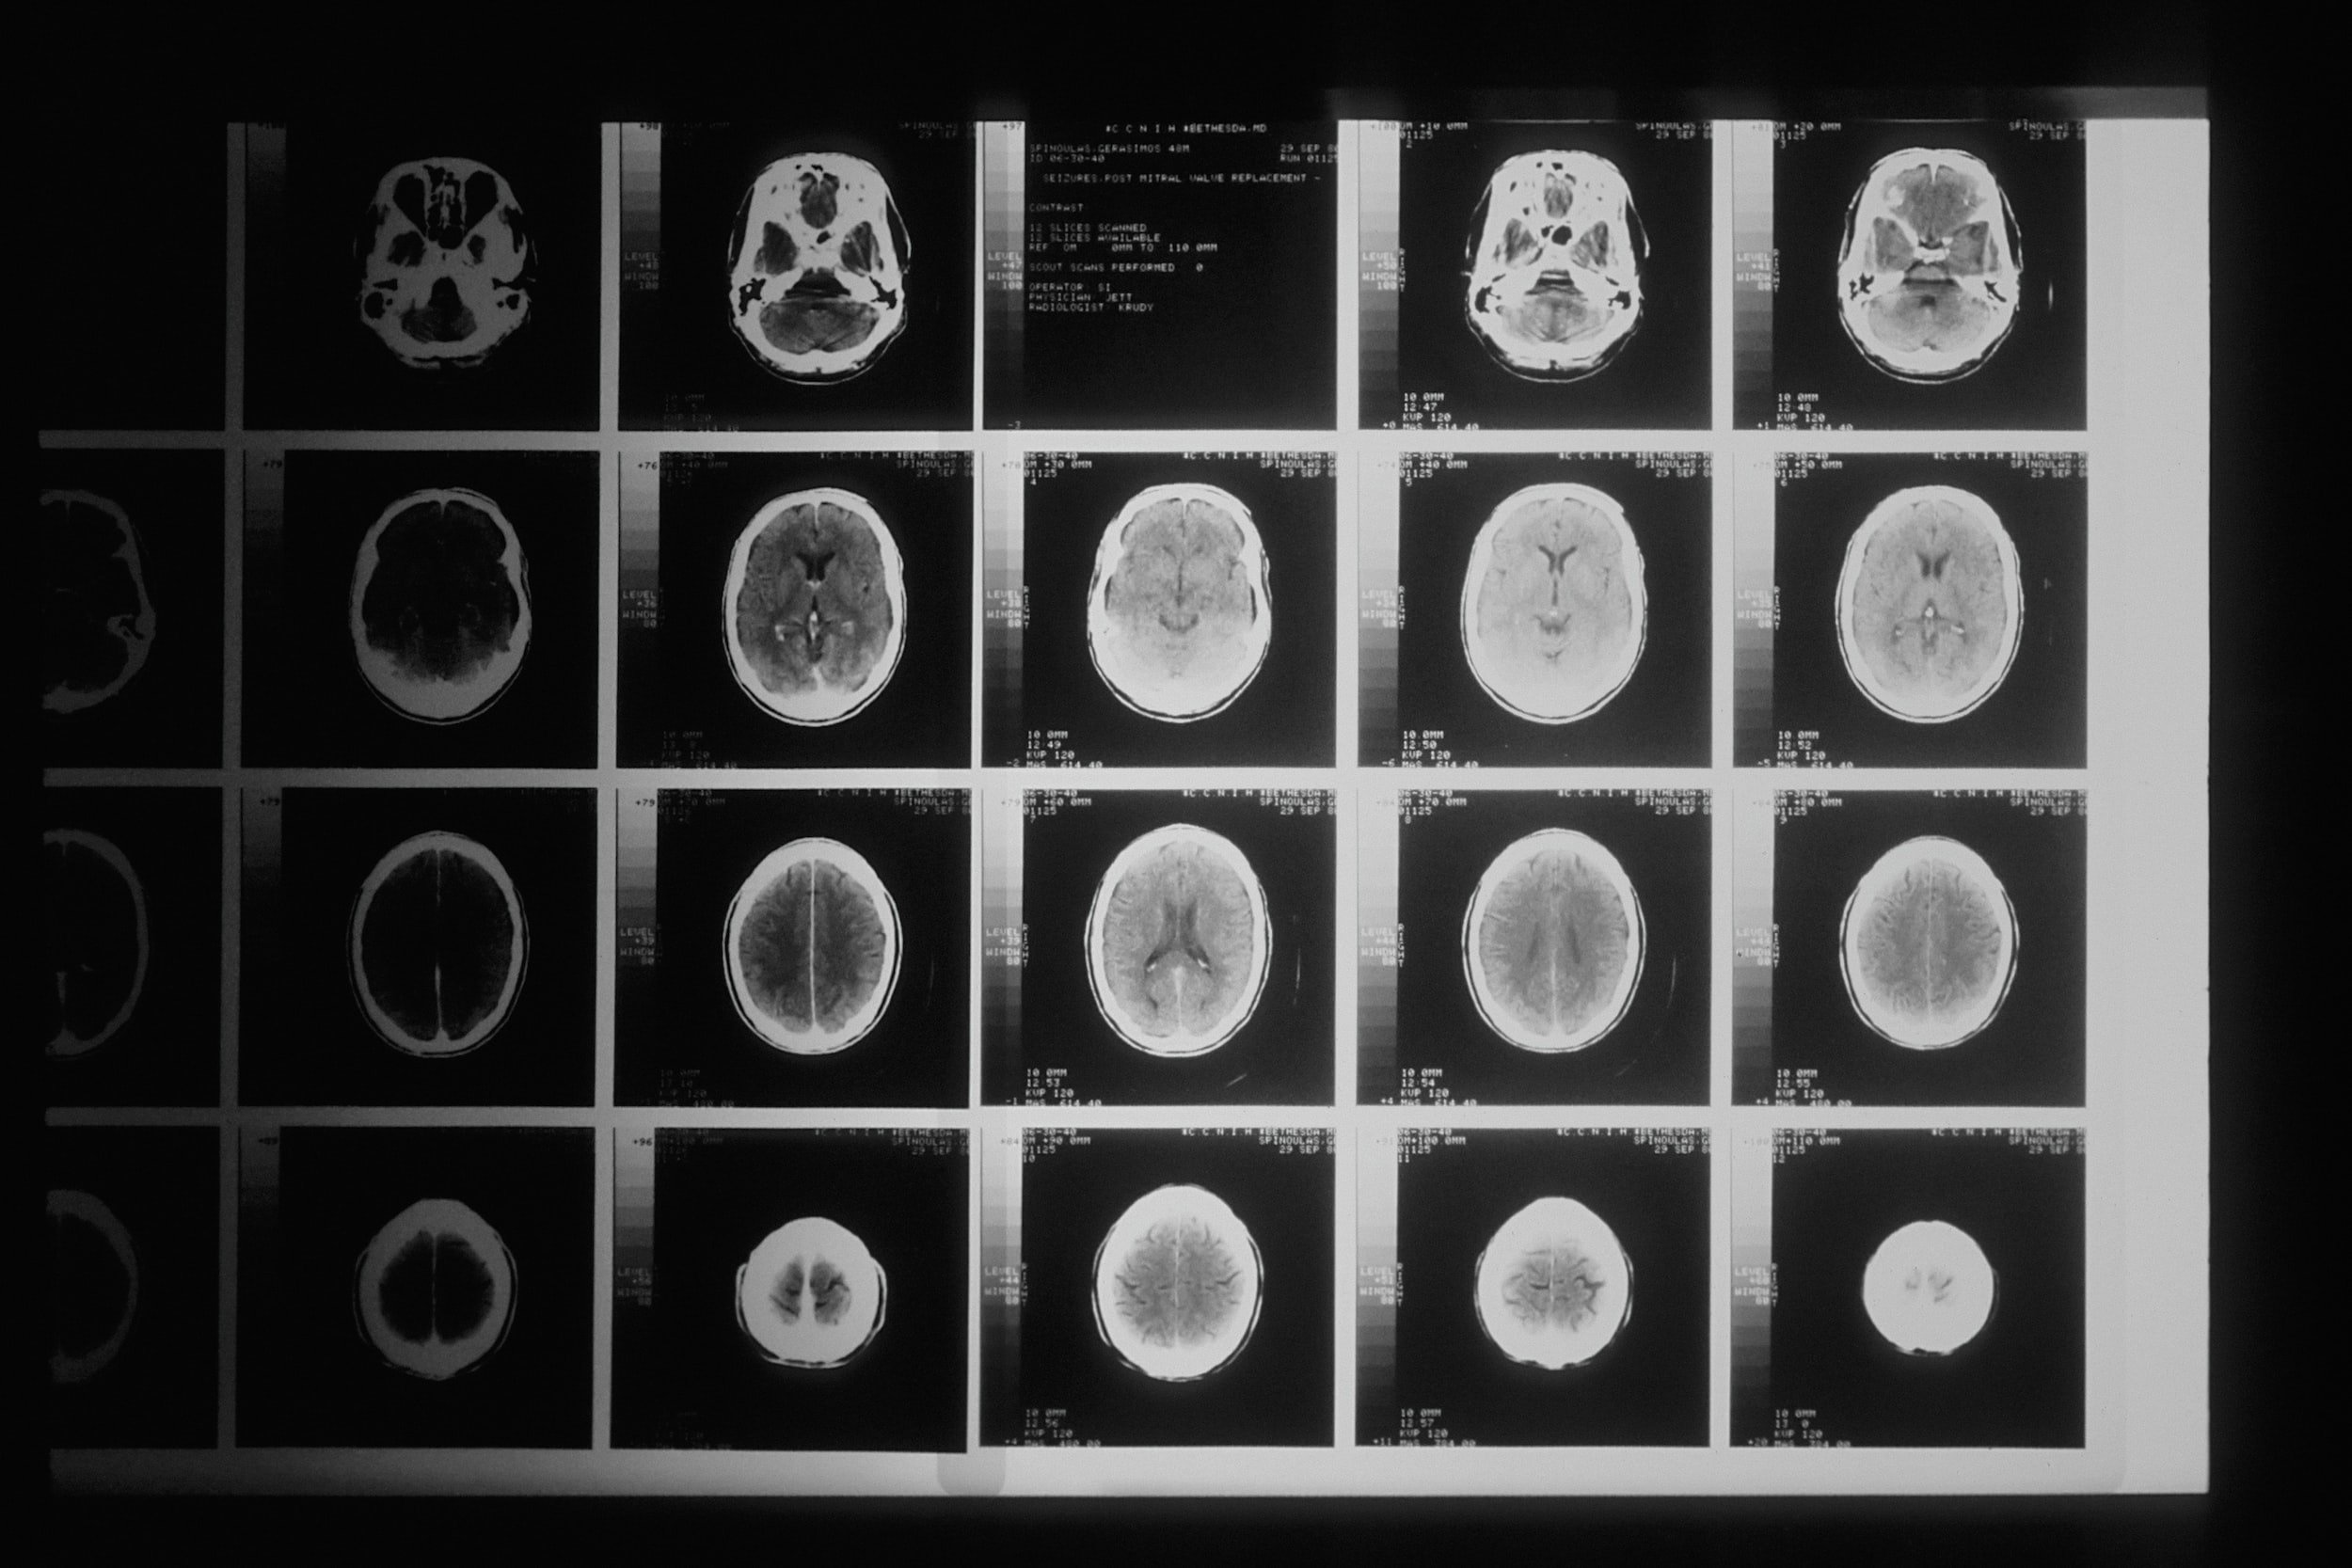

CSD

Cortical spreading depolarization (CSD) is thought to effect the recovery after a TBI. If we can detect and minimize the effects of these spreading depolarizations, we can improve recovery outcomes. This study is for moderate to severe TBI and does not actively recruit.

ClinicalTrials.gov identifier (NCT number): NCT03321370

Depth

This study is similar to the CSD study, but the mechanism of discovery is different. The depth study is using a single depth electrode in conjunction with novel analytical algorithms to detect CSDs in TBI patients. This study is for moderate to severe TBI and does not actively recruit.

ClinicalTrials.gov identifier (NCT number): NCT05205174